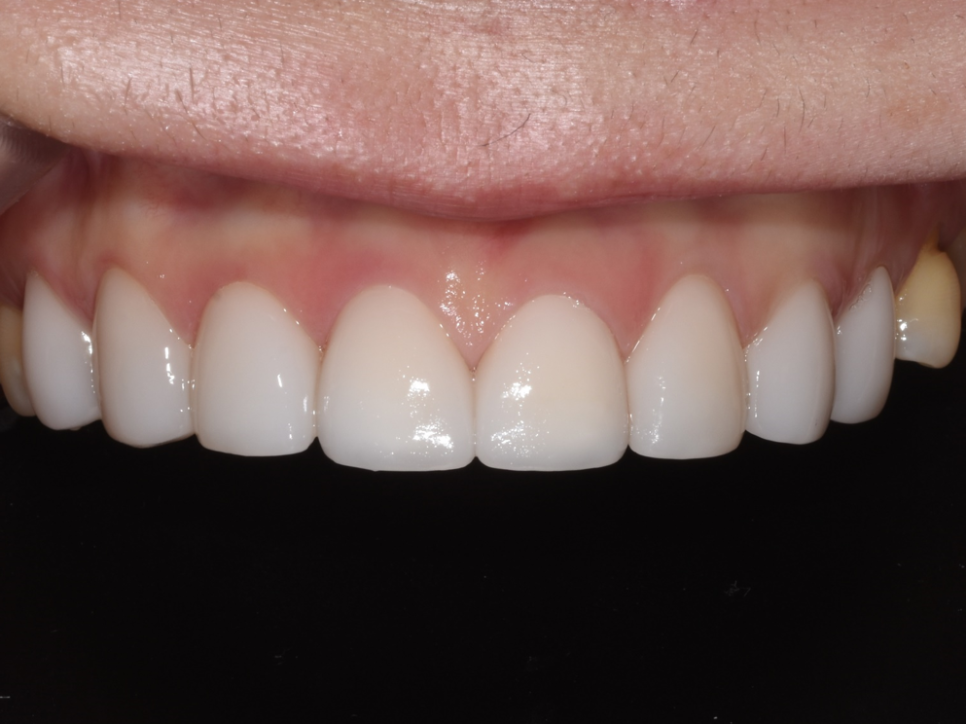

윗니 결과

밝고 균일한 색상, 자연스러운 형태, 환자분 희망 스타일과 거의 일치함

윗니는 정말 극적인 변화를 보여줍니다. 누렇던 색상이 밝고 균일한 톤으로 개선되었고, 레진 수복 흔적은 완전히 사라졌습니다. 돌출되었던 가운데 앞니 두 개는 자연스럽게 정렬되었고, 치아 사이에 있던 검은 삼각형도 깔끔하게 폐쇄되었습니다.

특히 잇몸성형을 병행한 덕분에 잇몸 라인도 고르게 정리되어 전체적으로 훨씬 조화로운 모습이 되었습니다. 환자분이 처음에 보여주셨던 레퍼런스 사진의 스타일과 거의 일치하는 결과물이 완성되었습니다.